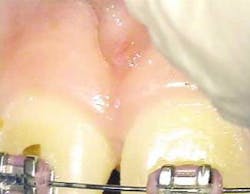

The following is a case report of one such procedure using the Opus Duo, a dual Er:YAG and CO2 dental laser system. This case begins with the diagnosis of a frenal attachment connected to the interdental papilla between maxillary central incisors (No. 8 and No. 9). The muscle attachment is bulky, and would inhibit further orthodontic correction. This patient was referred by her orthodontist for a minimally invasive laser frenectomy procedure before the next stage in her orthodontic treatment (figure 1).

After infiltration of 1cc of local anesthetic solution, the Er:YAG laser (OpusDuo, OpusDent USA) was used at 350mj with a 1,000-micron, contact sapphire tip and heavy water spray to gently ablate the frenal attachment and underlying muscle tissue down to the level of the periosteum (figures 2, 3, and 4). Once this is accomplished, there is a small defect in the vestibular mucosa and interdental papilla where the frenal attachment and muscle once was. There is no charring, no burned tissue, and free bleeding in the site (figure 5).